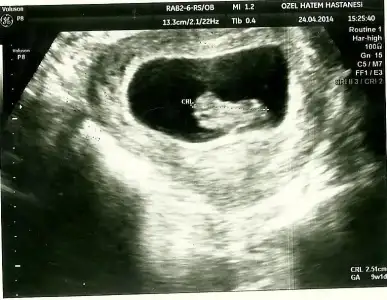

Eki Görüntüle 473831 simdi burada cikintilara bakin eger bel popo cizgisine paralel ise kiz

yok 30 derecelik bir aciyla yukari bakiyorsa erkek

Eki Görüntüle 473837 bu benim kizim cikinti gayet net ve ortada ve ben kizim diyooo